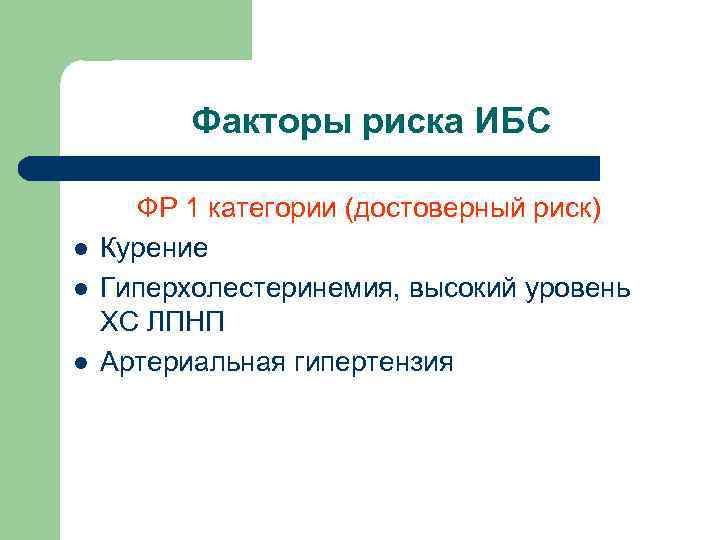

Факторы риска ИБС l l l ФР 1 категории (достоверный риск) Курение Гиперхолестеринемия, высокий уровень ХС ЛПНП Артериальная гипертензия